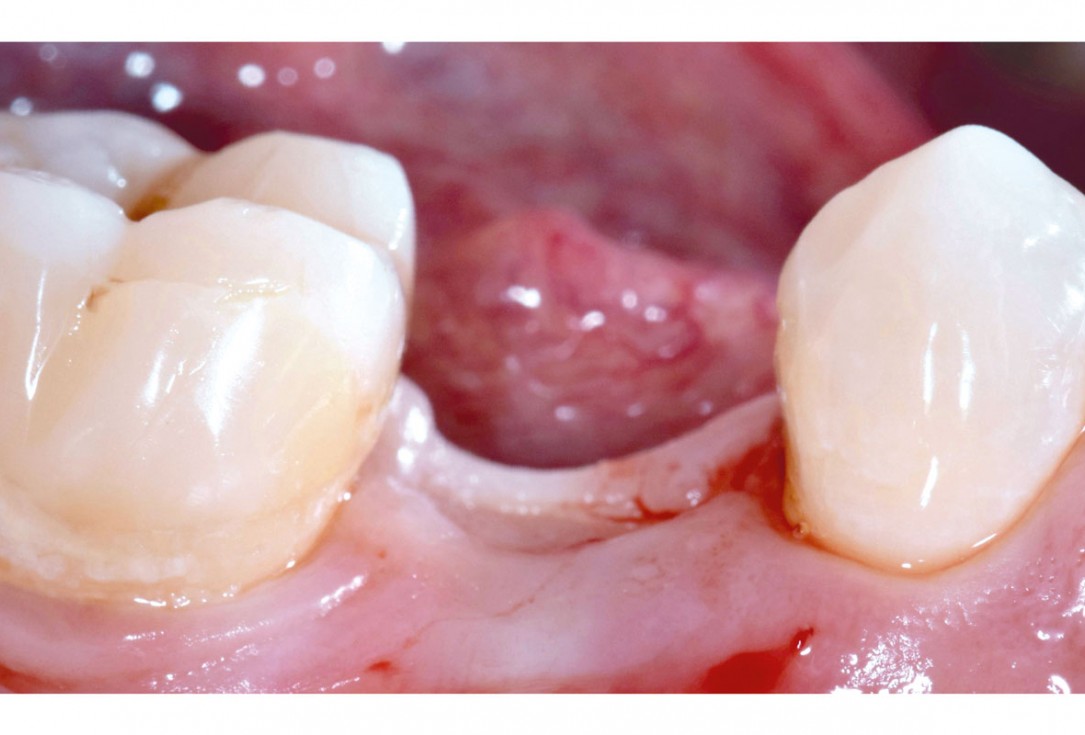

5/17 - Healing of the extraction socket at 3 monthsApplication of mucoderm® for soft tissue management around single implants at second stage surgery Dr. C. De Annuntiis